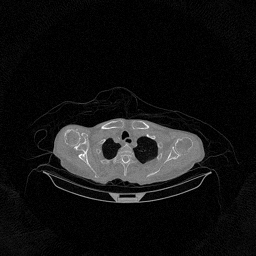

The experimental results on clinical head data are shown in Fig. 4. The reference images were reconstructed using the fast iterative shrinkage-thresholding algorithm (FISTA) with total variation regularization from non-truncated projection data. In the WCE reconstructions (Fig. 4(b)), severe truncation prevents accurate recovery of anatomical structures outside the FOV. Despite being trained solely on simulated data with a domain gap, all deep learning models can restore a substantial portion of the missing anatomy. Among them, the diffusion-based methods recover soft-tissue boundaries more faithfully than the conventional deep learning approach FBPConvNet, highlighting their stronger image generation capability. However, cDDPM reconstructions exhibit more noticeable noise than those from other methods, consistent with the simulated data results. The patchDiffusion model introduces artifacts within the FOV, likely due to its patch-wise processing strategy. While I2SB shares the same limitations as other diffusion models in perfectly restoring soft-tissue detail, it produces fewer residual noise patterns and fewer artifacts within the FOV boundaries. Overall, Fig. 4 demonstrates the strong efficacy of I2SB in reconstructing real CBCT data.